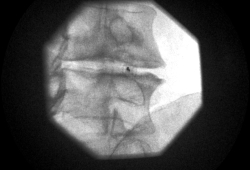

In de behandelzaal neemt de patiënt plaats op de behandeltafel in buikligging. Er wordt een pijnstillend en een licht kalmerend middel toegediend. Het aanprikken gebeurt met behulp van röntgendoorlichting. Eens de plaatsbepaling gebeurd is wordt de rug ontsmet om infectierisico te beperken. De huid wordt lokaal verdoofd. Dit kan branderig aanvoelen. Een naald wordt ingebracht tot in de discus. Daarna wordt een contrastmiddel ingespoten. Zowel de eventuele pijn die de patiënt hierbij ervaart als de structuur van de discus wordt hierbij geëvalueerd.